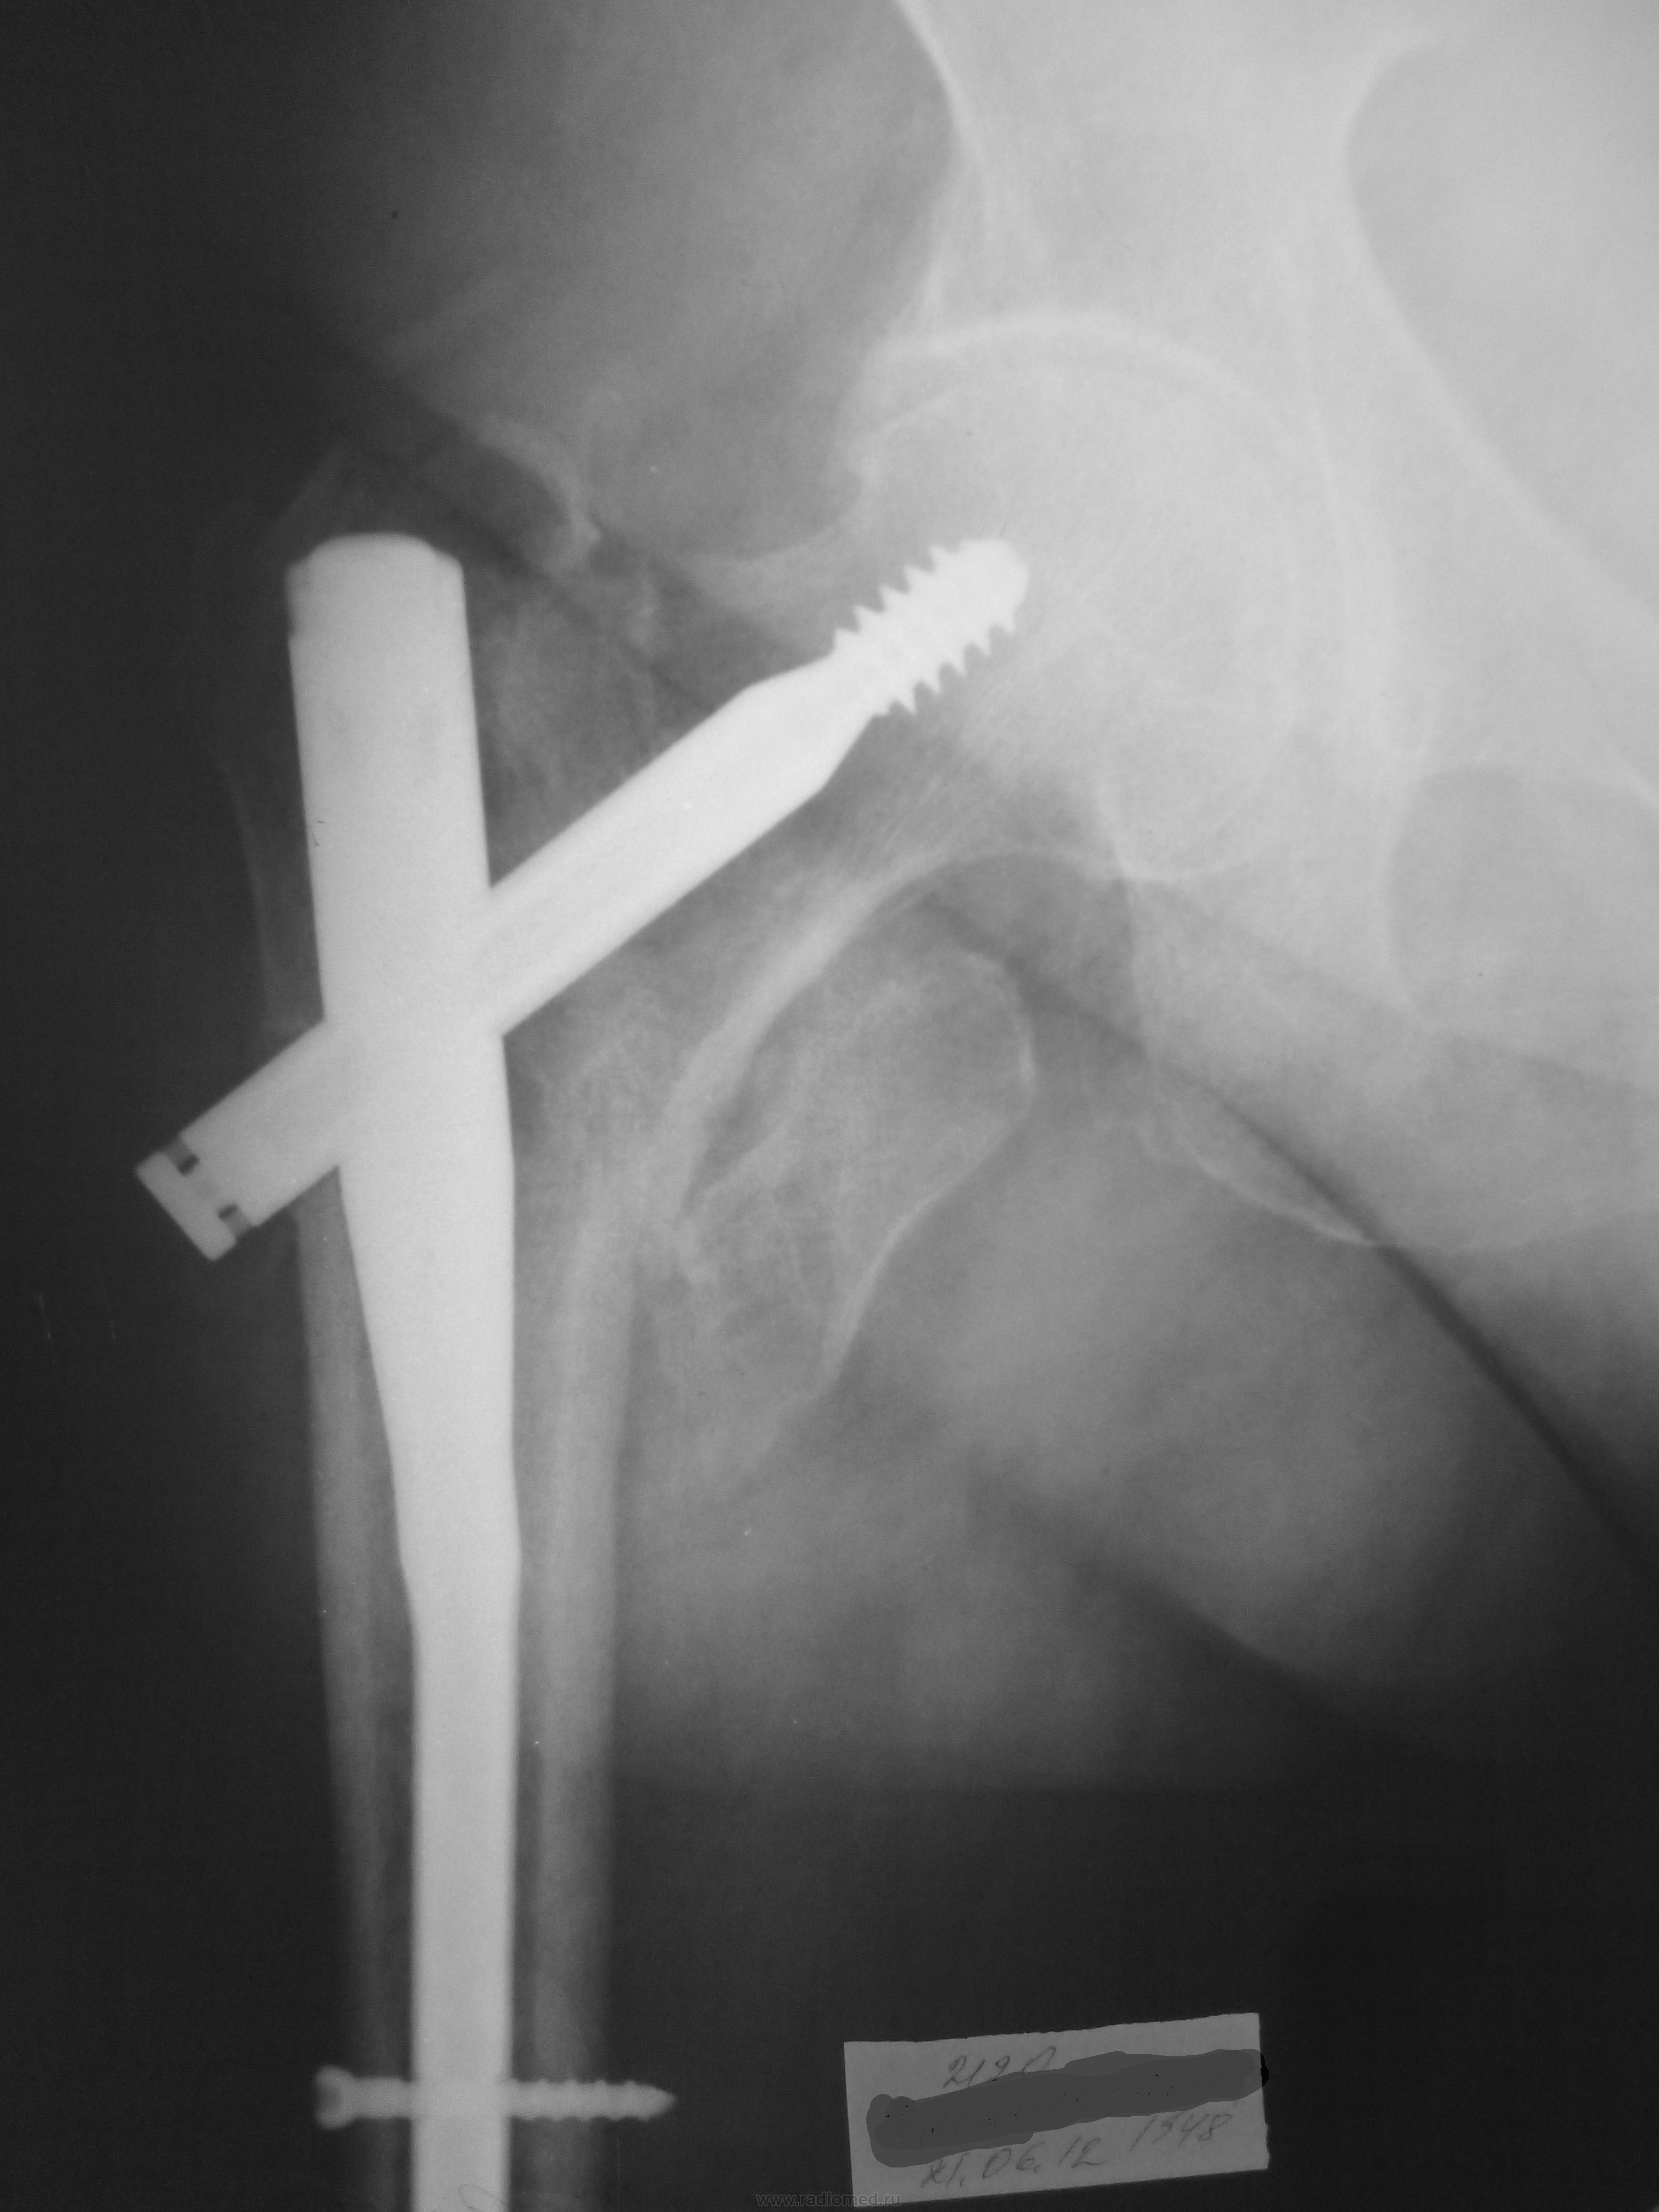

женщина 48 г.р. пришла на рентгенографию тазобедренного сустава,с остеосинтезом сталкиваюсь не часто,интересует должны ли части металлоконструкции так выходить за пределы кости ,так и было "задумано" или такого быть не должно?По медиальному контуру шейки бедра костный фрагмент-несросшийся перелом малого вертела?![]()

Металлоконструкция стоит нормально. Что же касается фрагмента, то скорее всего был чрезподвертельный перелом и, действительно, с отрывом малого вертела. Только вот диастаз по верхнему краю шейки сохраняется. Сколько времени после МОС?

Металлоконструкция действительно стоит нормаль, тут недостаточная вальгизация была во время операции:маленький диастаз между отломками по верхнему краю и не по центру шейки прошол винт. в общем ни плохо. Сколько времени прошло после операции? где делали?

для полной картины нужна вторая проекция (аксилярная) в идеальном варианте

удовлетворительный МОС, малым вертелом пренебрегаем